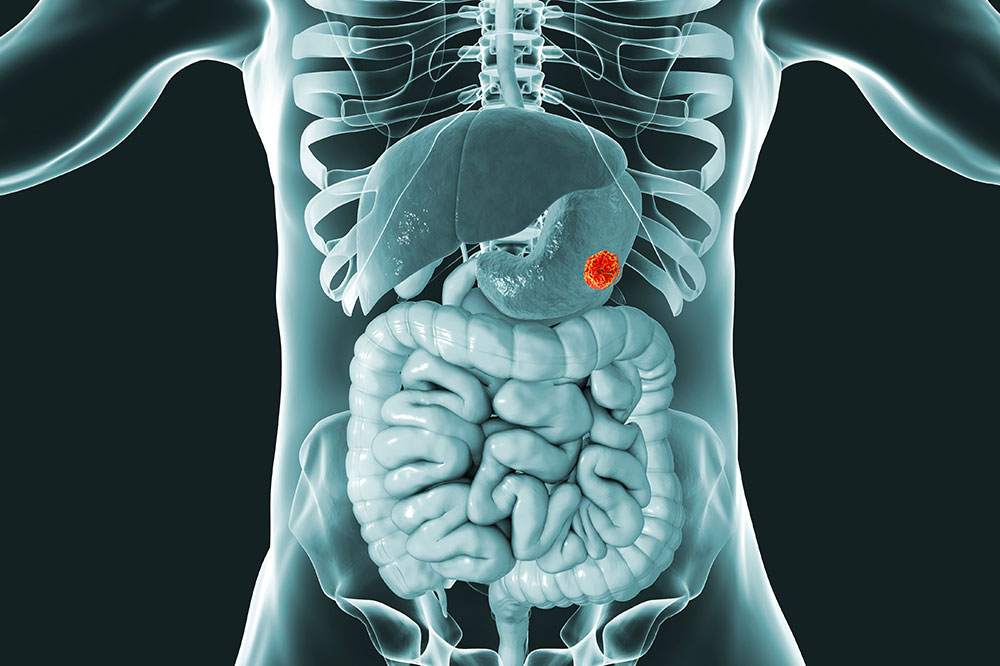

GIST- Symptoms, causes and treatment options

A gastrointestinal stromal tumor (GIST) is a type of tumor formed by the abnormal growth of cells in the gastrointestinal linings. The tumor can be observed anywhere along the digestive tract, but it is most commonly observed in the stomach and small intestine. The abnormally growing cells have the potential to develop into cancer, and therefore must be addressed immediately.